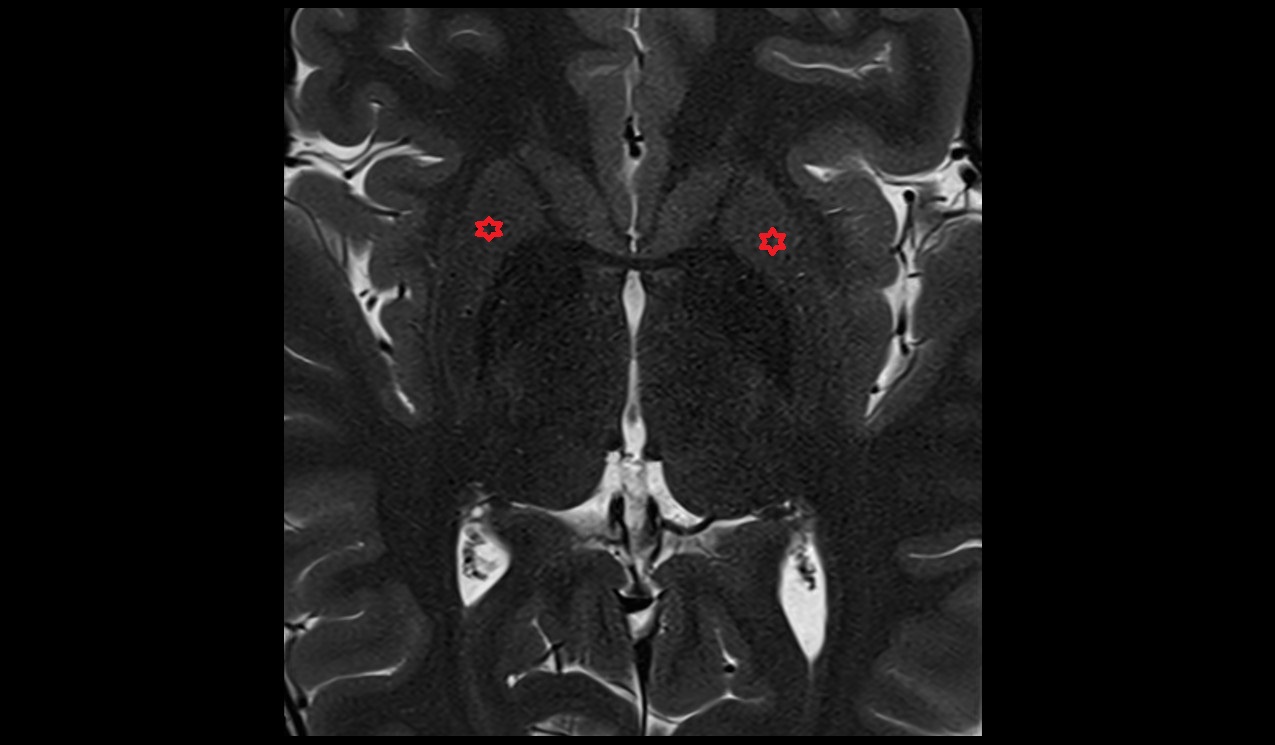

- Hippocampus